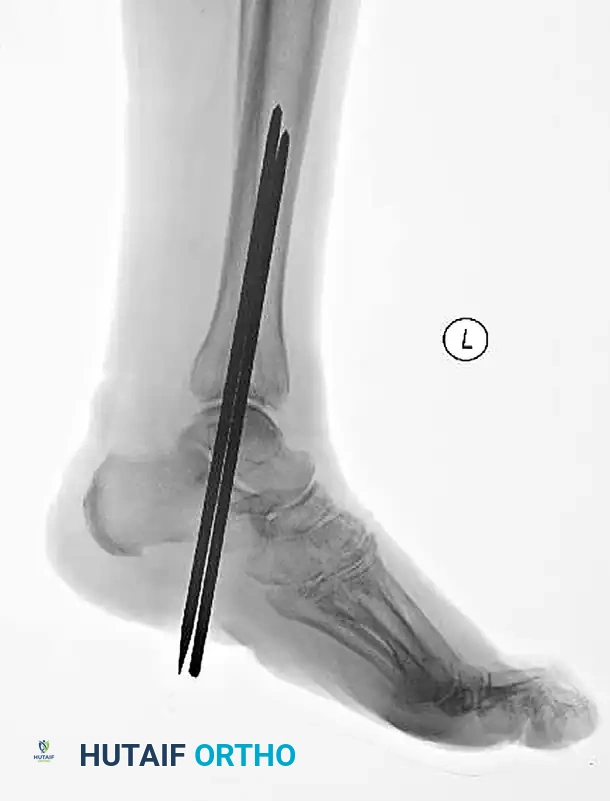

The following preoperative and postoperative radiographs demonstrate the successful application of augmented fixation in a young diabetic patient with a severe bimalleolar fracture-subluxation:

FIGURE 85-25 A and B: Preoperative radiographs of a highly unstable bimalleolar ankle fracture-subluxation in a 19-year-old man with a 12-year history of insulin-dependent diabetes mellitus.